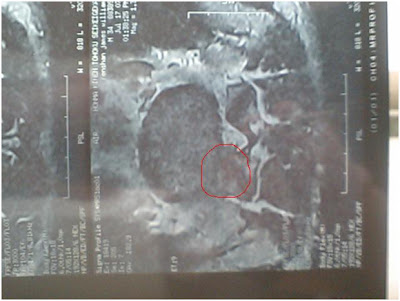

A bad disk